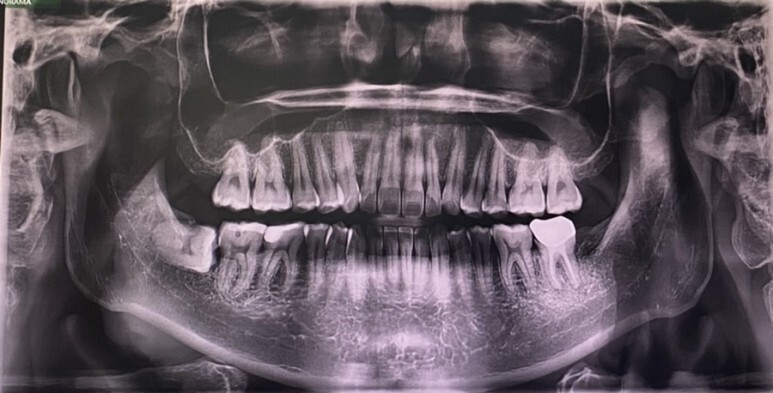

ct, x-ray 찍고 대기하였습니다.

바로 오늘 제거해야 할 녀석인데

오른쪽 저 녀석입니다.